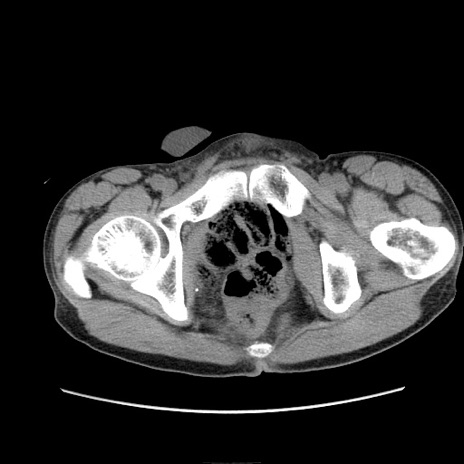

症例11(横断像)

【症例】 60歳代男性

【主訴】 下腹部痛

【現病歴】 本日夜中より下腹部痛の症状認め、受診。

【既往歴】 膀胱癌(膀胱全摘+尿管皮膚瘻術) 、胃癌術後

【身体所見】 BT 35.3℃、PR 58/min、BP 136/98mHg、腹部平坦、軟、腸蠕動音±、ストマ留置あり、左上腹部~正中部に圧痛あり、反跳痛なし。

【データ】WBC 5100、CRP0.01